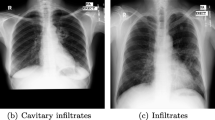

Chest radiography is the most preferred non-invasive imaging technique for early diagnosis of Tuberculosis (TB). However, lack of radiological expertise in TB detection leads to indiscriminate chest radiograph (CXR) screening. A modest classification approach based on the local image description to detect subtle characteristics of TB using CXRs is highly recommended. In this work, an attempt has been made to classify normal and TB CXR images using Bag of Features (BoF) approach with Speeded-Up Robust Feature (SURF) descriptor. The images are obtained from a public database. Lung fields segmentation is performed using Distance Regularized Level Set (DRLS) formulation. The results of segmentation are validated against the ground truth images using similarity, overlap and area correlation measures. BoF approach with SURF keypoint descriptors is implemented to categorize the images using Multilayer Perceptron (MLP) classifier. The obtained results demonstrate that the DRLS method is able to delineate lung fields from CXR images. The BoF with SURF keypoint descriptor is able to characterize local attributes of normal and TB images. The segmentation results are found to be in high correlation with ground truth. MLP classifier is found to provide high Recall, Specificity (Spec), Accuracy, F-score and Area Under the Curve (AUC) values of 87.7%, 85.9%, 87.8%, 87.6% and 94% respectively between normal and abnormal images. The proposed computer aided diagnostic approach is found to perform better as compared to the existing methods. Thus, the study can be of significant assistance to physicians at the point of care in resource constrained regions.